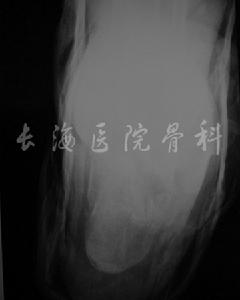

跟骨骨折影像病人有典型的外傷史,患足承重困難和足跟疼痛,局部觸痛、腫脹和皮下淤血斑亦多明顯。在較嚴重的壓縮骨折時,除可見到足後跟的高度變低和足跟橫徑變寬以及外踝下部正常凹陷消失外,距下關節話動亦完全喪失。但跟骨周邊骨折僅有局部腫脹及壓痛,而距下關節活動範圍多屬正常。x線正、側、軸位片可明確跟骨的結節關節角和其橫徑寬度的改變。

(5)接近跟距關節的骨折為跟骨體的骨折,損傷機制亦為高處跌下跟骨著地,或足跟受到從下面向上的反衝擊力量而引起。骨折線為斜行。X線片正面看,骨折線由內後斜向前外,但不通過跟距關節面。因跟骨為骨松質,因此軸線位觀,跟骨體兩側增寬;側位像,跟骨體後一半連同跟骨結節向後上移位,使跟骨腹部向足心凸出成搖椅狀